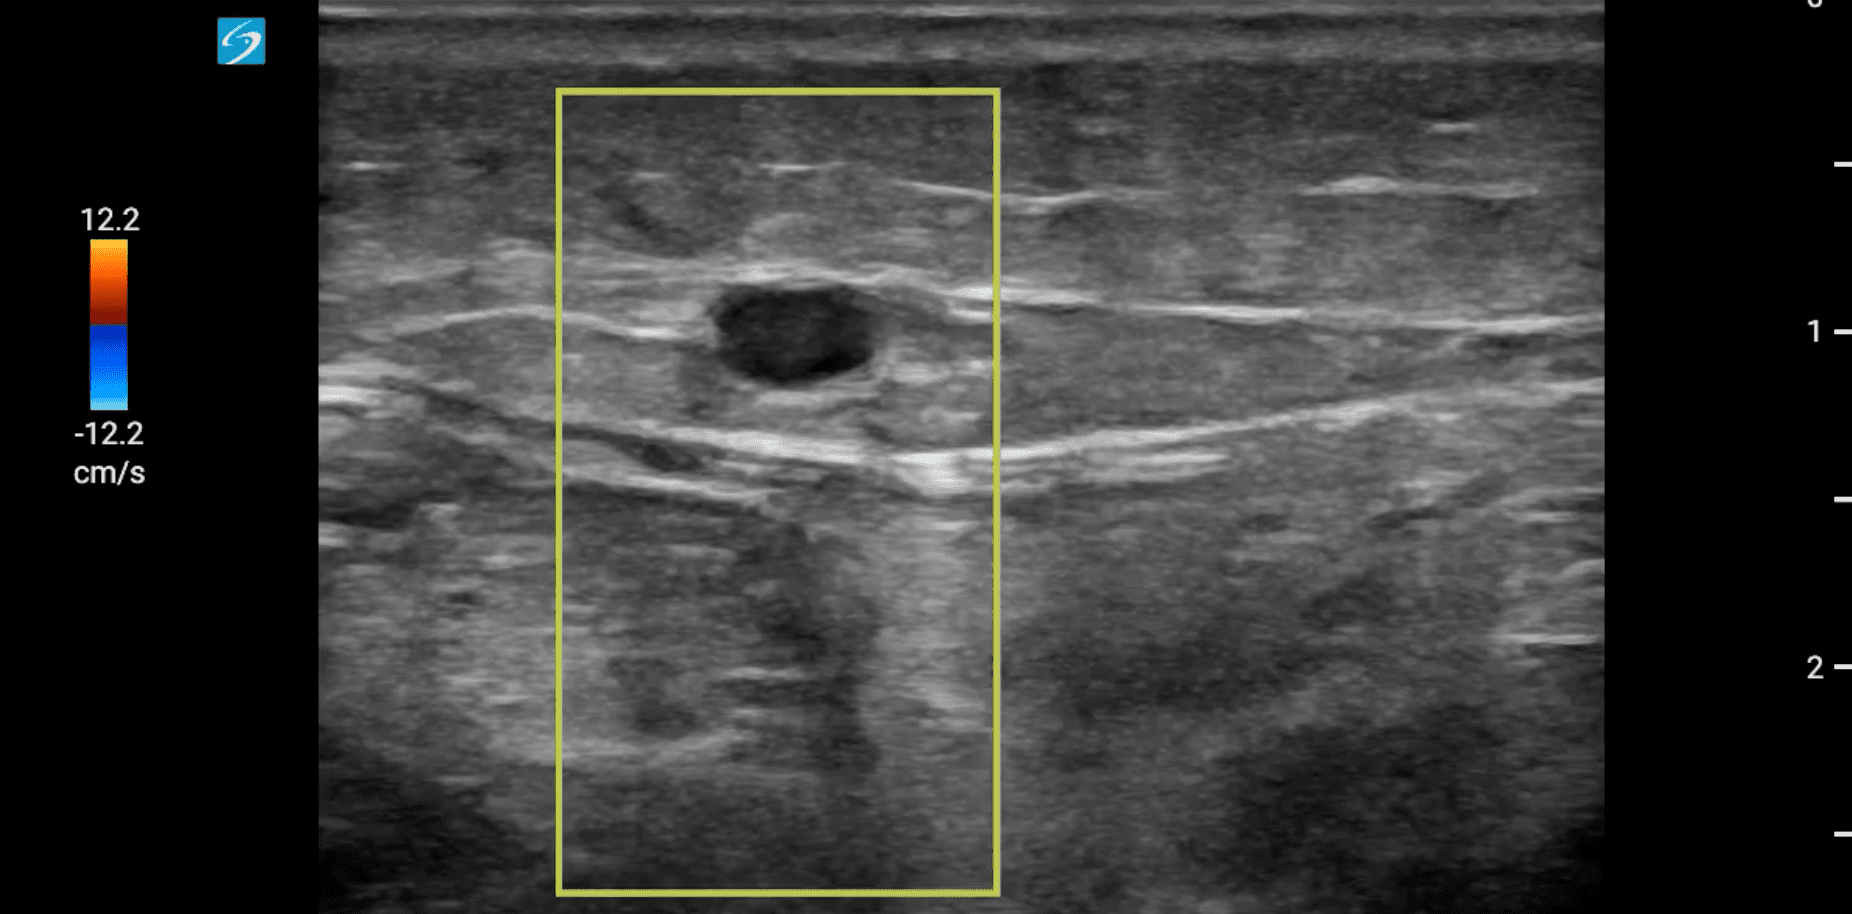

Se localiza ecográficamente la vena femoral común con una imagen hipoecogénica que no colapsa con a la compresión y que se extiende por femoral superficial hasta poplítea. Tras hallazgos, se realiza también una ecografía cardíaca, con un diámetro de visu VD/VI < 1 y con una función cardíaca conservada, con resultado en escala PESI de riesgo bajo.

Como diagnóstico diferencial se valoran celulitis e insuficiencia venosa crónica. Se realiza una ecografía reglada que confirma el diagnóstico de sospecha de trombosis venosa profunda (TVP) extensa subaguda.